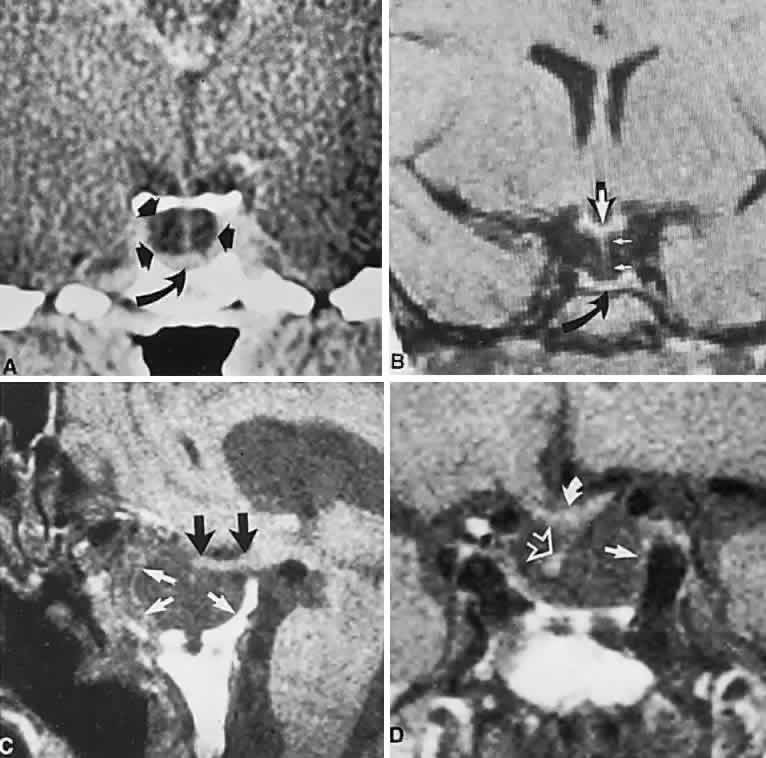

CT scanning retains special relevance to craniopharyngioma diagnosis, currently superior to MRI in detection of calcification and cyst formation (Fig. 7A to C); however, the extent of involvement of adjacent structures, that is, the optic chiasm, third ventricle, and intracavernous carotid artery, is more clearly delineated by MRI (Fig. 7D and E).93 Craniopharyngioma fluid collections are found to be uniformly bright on T2-weighted sequences, but on T1-weighted images, the signal intensity may range from hypointense to hyperintense, reflecting the heterogeneous contents of cysts. Because calcification and cyst formation are hallmarks of craniopharyngiomas, CT is more specific than MRI. At times, intrinsic infiltration of tumor may thicken the chiasm and contiguous optic nerve, a radiologic configuration that mimics glioma.94 Likewise, glioma may be simulated when the optic canal is invaded and enlarged, but accompanying bony erosion of the sella weighs heavily toward craniopharyngioma.

Fig. 7. Computed tomography scan of a large, multicystic craniopharyngioma. A. Axial section through the sella shows destruction of the bony skull base. Axial (B) and coronal (C) sections show cysts (white arrows) and calcification (arrowheads). Contrast-enhanced magnetic resonance imaging of the craniopharyngioma. Sagittal (D) and coronal (E) sections with gadolinium show solid and cystic (arrows) portions.